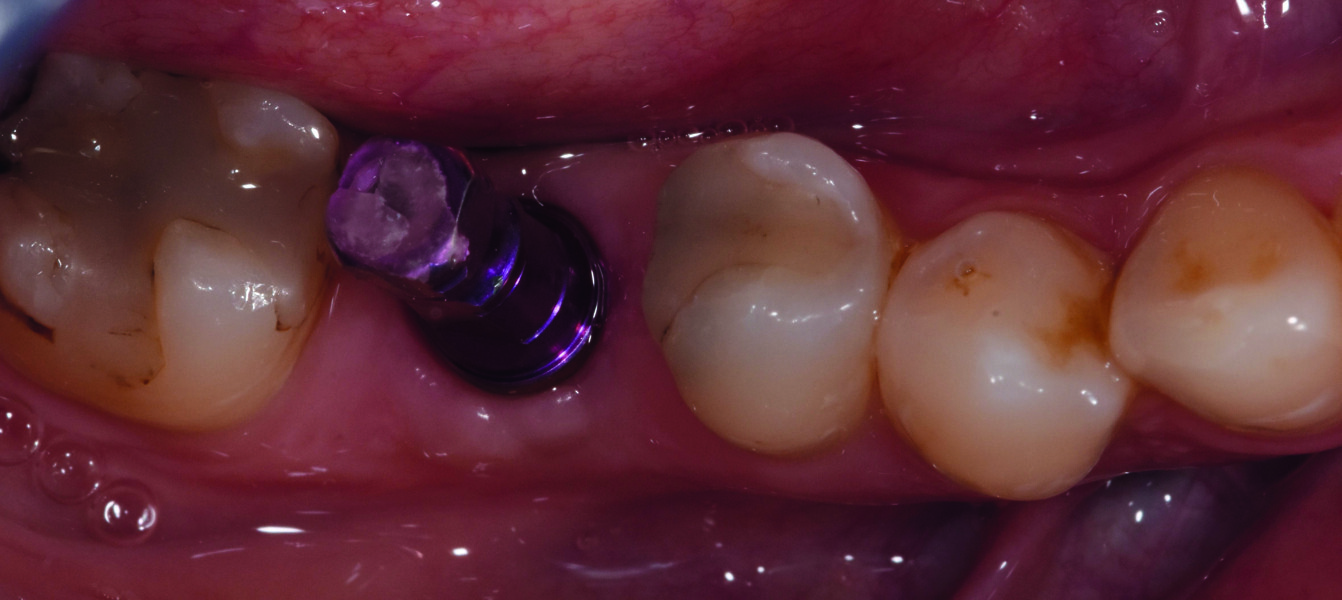

Pose de l’implant Pose d’un implant Seven de MIS au niveau de la 46. Ces dimensions 5/11.5 mm permettent l’obtention d’une bonne stabilité primaire dans l’alvéole. Mise en place de la vis de couverture et fermeture du site.

Trois mois plus tard. Second temps du protocole en deux temps. Légère incision crestale, dépose de la vis de couverture et ensuite mise en place de la vis de cicatrisation (Fig. 14).

Fig. 14 : Vue occlusale du pilier de cicatrisation vissé dans le col implantaire.